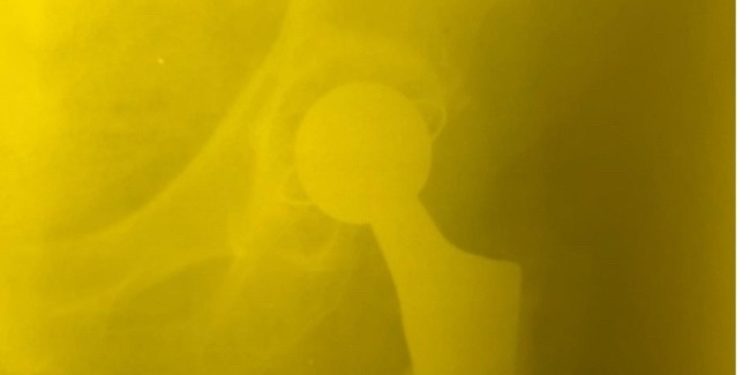

Однако рязанские доктора провели эндопротезирование тазобедренного сустава и полностью восстановили длину конечности.